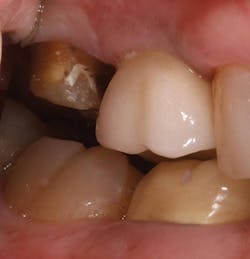

My first step in treatment was to create an access hole in the central fissure, where I then inserted a 2 mm reduction bur (Kometas, www.occlusalbur.com). In my opinion, this is the only way to guarantee adequate reduction to a tooth during preparation (Fig. 3). As you can see in Fig. 4, there does appear to be adequate clearance from a side view. However - and I cannot emphasize this enough - there is a significant difference between occlusal clearance and occlusal reduction. Fig. 5 clearly shows the preparation mark remaining following penetration with the 2 mm reduction bur mentioned previously. Following final preparation, another photo was taken from the side showing the preparation following adequate reduction (Fig. 6).

FIG. 3

FIG. 4